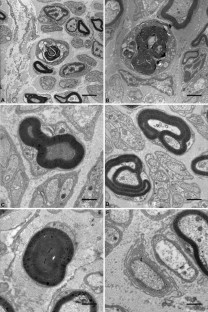

Spinal muscular atrophy with respiratory distress type 1 (SMARD1) is genetically and clinically distinct from classic spinal muscular atrophy (SMA1). It results from mutations in the gene encoding immunoglobulin μ-binding protein 2 (IGHMBP2) on chromosome 11q13. Patients develop distally pronounced muscular weakness and early involvement of the diaphragm, resulting in respiratory failure. Sensory and autonomic nerves are also affected at later stages of the disease. We investigated peripheral nerves, skeletal muscles and neuromuscular junctions (NMJ) ultrastructurally in five unrelated patients and three siblings with genetically confirmed SMARD1. In mixed motor and sensory nerves we detected Wallerian degeneration and axonal atrophy similar to the ultrastructural findings described in SMA1. Isolated axonal atrophy was evident in purely sensory nerves. All investigated NMJ of patients with SMARD1 were dysmorphic and lacked a terminal axon. Moreover, we also observed characteristics of neuropathies, such as abnormalities in myelination, that have not been described in spinal muscular atrophies so far. Based on these findings we conclude that impairment of IGHMBP2 function leads to axonal degeneration, abnormal myelin formation, and motor end-plate degeneration.

Fig. 1 A